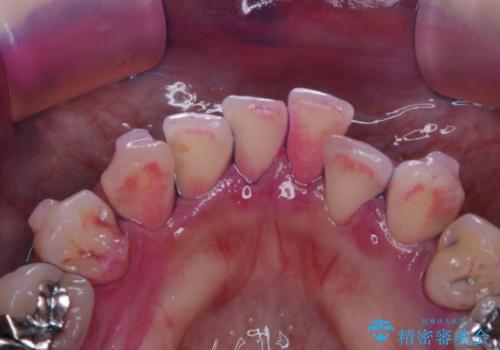

- インビザラインで矯正治療中にクリーニングを希望されました。PMTC60分コースで、クリーニングと歯ブラシ指導を行いました。

磨けているようでも、染出しをして目に見えるプラーク(歯垢)を確認することで、より正しいブラッシング方法を身につけることができます。インビザライン中は、歯にアタッチメントをつけるため、歯の表面がデコボコしてプラークが付きやすい状態になります。毎日のケアでしっかりと汚れを落として虫歯や歯周病・口臭のリスクを減らしていくことが大切です。定期的にメンテナンスを行い、ケアがどれくらい出来ているか確認したり歯科医院で専門的な機械や器具によるPMTCを行うことをおススメします。